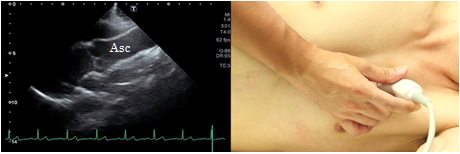

High intercostal approach

In the high intercostal approach, place the probe along the parasternal long axis at one or two intercostal spaces above the depiction position of the longitudinal parasternal view of the left ventricle and try to visualize it to the peripheral side of the ascending aorta. This view is suitable to observe lesions in the ascending aorta.